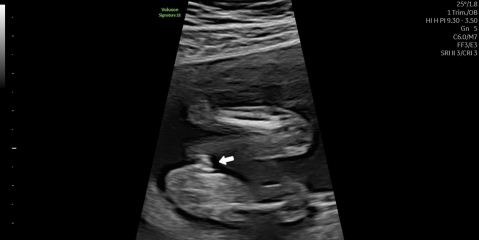

Unsure about gender scan result after conflicting opinions on the images

So we had our gender scan today at 16+3 and the potty shot isn’t as clear as my first child so curiosity had me put it into chat gpt and both pictures said the opposite gender🥲 so can I get some opinions please😂